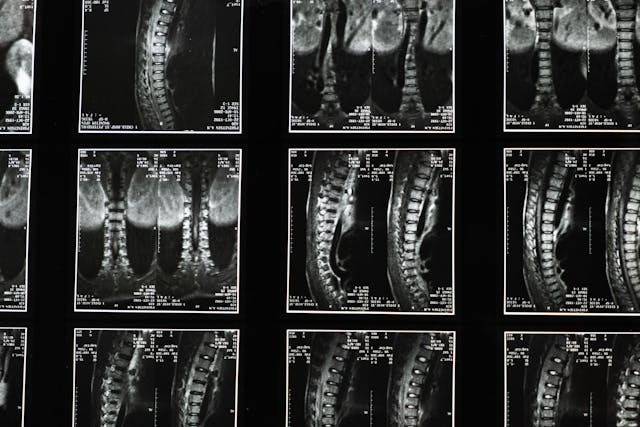

바닥에 엎드린 자세는

목에서 허리로 연결되는

정상적인 뼈 정렬을

무너뜨리게 됩니다

엉덩이와 등뼈가 꺾이면서

척추에 가해지는

압력이 커지고,

허리에 부담이 되면서

통증이 발생할 수 있는데요

만약 엎드린 채로

고개라도 돌리고 잠들게 되면

목 주변 인대가 손상되고

이는 나중에 디스크를

불러일으키게 됩니다